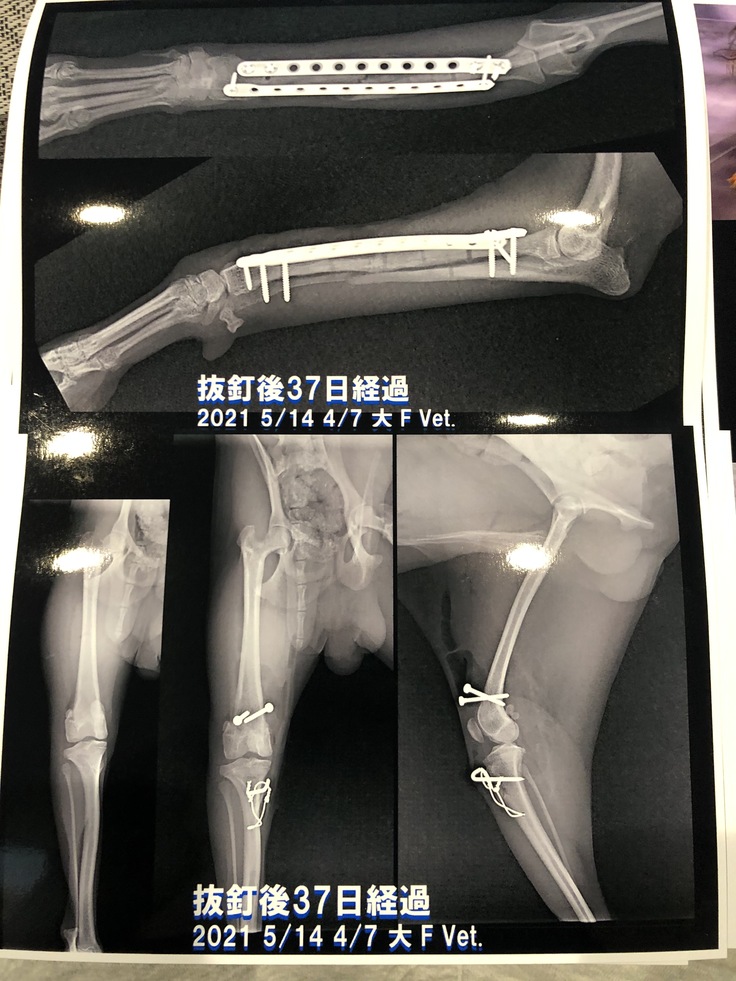

↑腕が湾曲してしまった際のレントンゲンです。

↑(身体に合ってないプレートのレントゲン写真)

手術は無事終わり、術後のレントゲンを見ると大きなスクリューホールが…

いかに大きいサイズのプレートが入っていたのか分かりました。

そして先生からは「前のプレートが大きかったから腕がどんどん曲がってしまっているので矯正する手術も必要な可能性がある」と言われました。

↓最新のレントゲン写真です